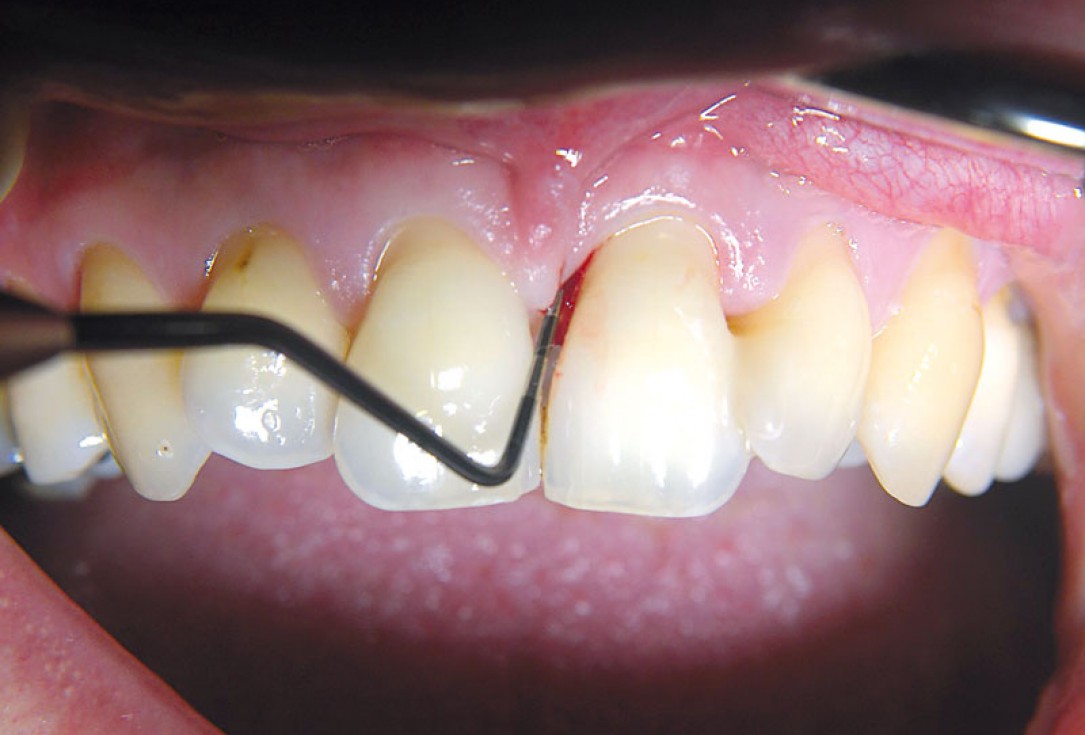

03/11 - Pre-surgical probing.Non-contained intrabony defect treated using cerabone®, collprotect® membrane and Straumann® Emdogain® - Dr. T. Schwaar (2)